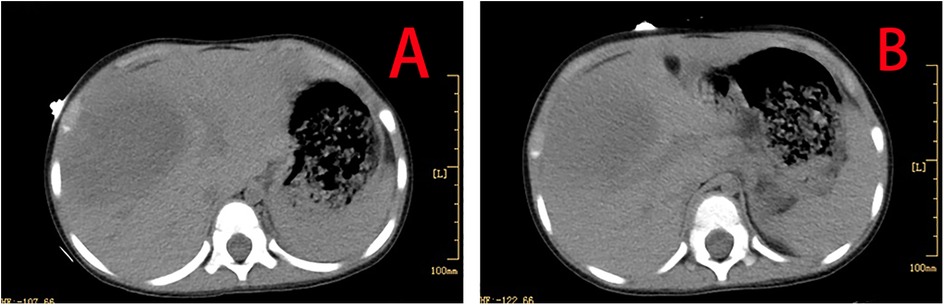

The Coombs test was positive, while the rheumatism screening returned negative results. Both Chlamydia pneumoniae IgG and Mycoplasma pneumoniae total antibodies were positive. Blood and bone marrow cultures were obtained. Echocardiography revealed no abnormalities in the left and right coronary arteries or their branches. Non-enhanced abdominal computed tomography (CT) showed hepatomegaly, with extensive low-density areas in the left inner and right anterior lobes of the liver, the nature of which was unclear (Figures 1A,B).

Figure 1. CT showing hepatomegaly, with extensive low-density areas in the left inner and right anterior lobes of the liver (A,B).